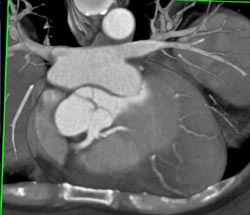

Left Main Off Right Coronary Artery